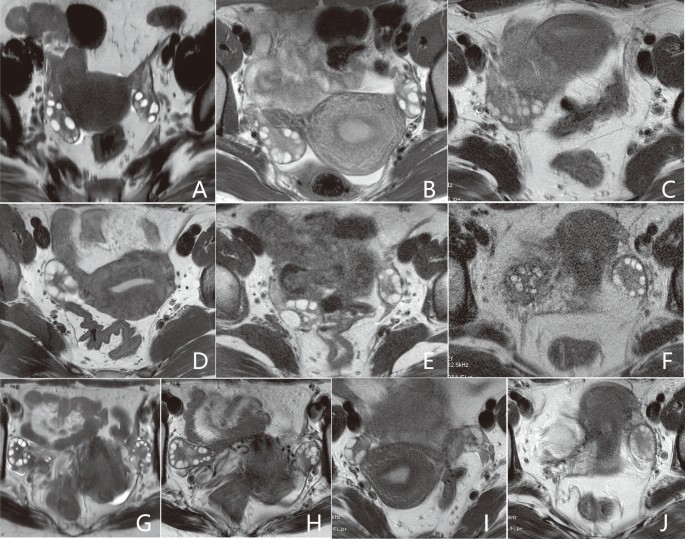

The assessment criteria included the evaluation of blurring artifacts on a 3-point scale (3 = almost no visible blurring artifacts, 2 = blurring present but not interfering with the visualization of follicles, 1 = blurring present and interfering with the visualization of follicles), subjective noise on a 3-point scale (3 = almost no visible noise, 2 = noise present but not interfering with the visualization of follicles, 1 = noise present and interfering with the visualization of follicles), and the conspicuity of follicles scored on a 4-point scale (4 = excellent, almost no visible artifacts with clear delineation of follicles; 3 = good, slight artifacts but without impairing follicle counting; 2 = moderate, moderate artifacts with partial impairment of follicle counting; 1 = poor, severe artifacts with unrecognizable delineation of follicles). Refer to Fig. 2 for illustration.

Scoring criteria for qualitative analysis. Scores of 3, 2, and 1 for blurring artifacts are assigned to (A–C), respectively. Scores of 3, 2, and 1 for subjective noise are assigned to (D–F), respectively. Scores of 4, 3, 2, and 1 for conspicuity of follicles are assigned to (G–J), respectively. Higher scores indicate better image quality.